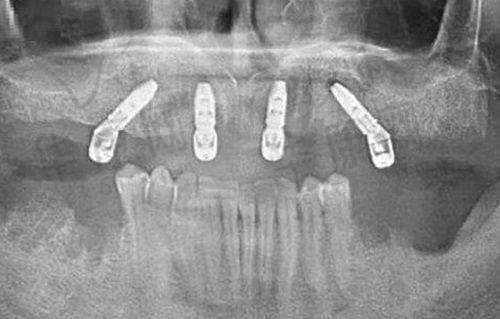

黑龙江美植口腔是本地品牌名气大的高端连锁现代化齿科。该医院有来自哈医 大一院、哈医 大二院、哈医 大四院、中华口腔医学会等公办机构的超名气医生坐诊。这些医生掌握精良口腔诊疗技术,擅长牙齿疑难种植、复杂正畸等现代化口腔治疗项目。